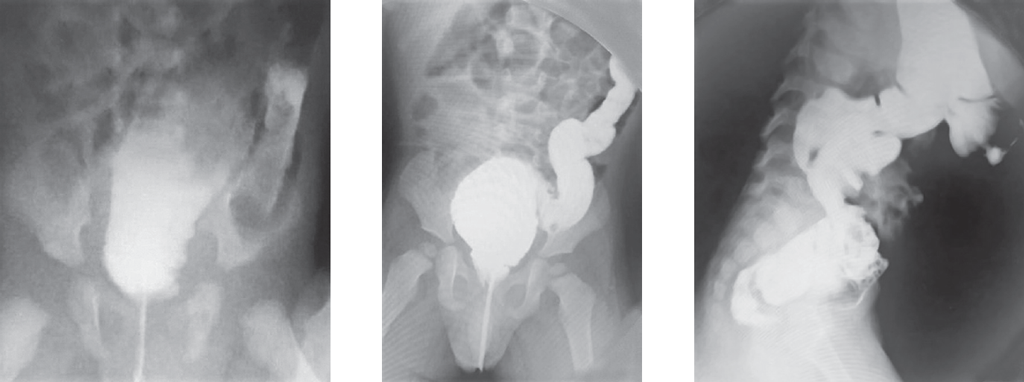

Hirschsprung’s disease usually manifests from the first days of life and is diagnosed in the newborn period. In some patients Hirschsprung’s disease can’t be diagnosed in the newborn period because of different forms of disease and clinical features. From 2008 to 2019 75 patients with Hirschsprung’s disease were operated in the City Children’s Hospital No. 1. 21 patients had delayed diagnosis. 11 newborns didn’t have very clear clinical symptoms, intestinal obstruction disappeared after decompression. 2 patients with associated chromosomal disorders were diagnosed with Hirschsprung’s disease later because of. In some of older patients disease manifested with severe constipations. Also, we presented some clinical cases of major diagnostic errors in patients with Hirschsprung’s disease. Conclusion. Diagnostic errors in patients with Hirschsprung’s disease are associated with the lack of alertness of neonatologists and inadequate interpretation of clinical manifestations and X-ray study. For many years these children can be treated by different specialists before having surgical consult.